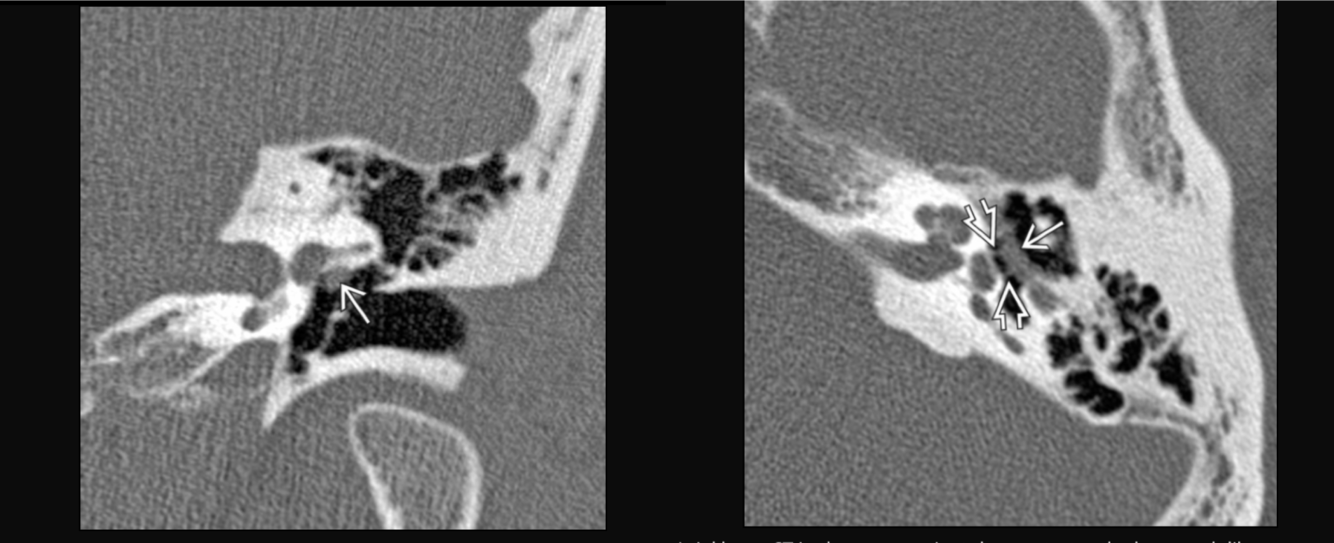

Prolapsing facial nerve (protruding intratemporal facial nerve)

Tubular soft tissue prolapsing into oval window niche from undersurface of LSC. Caused by dehiscence of bony covering of the facial nerve.

No enhancement! If enhances then it is a Schwannoma.

May project into oval indow.